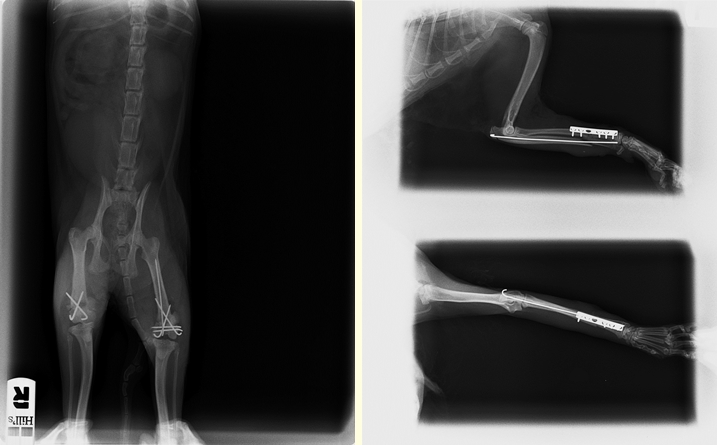

Telmo y Aisha van recuperándose. Ayer a Telmo le quitaron la medicación. Aisha todavía tiene que tomar, ya que las patitas de atrás todavía tienen que dolerle. Este es el informe veterinario y algunas radiografías:

En la exploración inicial no se detecta ninguna lesión de riesgo vital y se detectan varias fracturas. Presenta fractura supracondilar transversal con fractura del cóndilo en ambos fémures. También presenta una fractura diafisaria transversal del radio y cubito izquierdo además de una rotura del paladar.

En una primera intervención se procede a la resolución de las dos fracturas de fémur y del paladar. La gata se recupera con normalidad de la intervención pero desarrolla una anemia hemolítica. Con el tratamiento se recupera con normalidad pudiéndose realizar una segunda intervención para solucionar la fractura de cúbito y radio con una placa de osteosíntesis. En esta intervención se detecta que una de las fijaciones de la rodilla se ha desplazado por una fisura del fémur, la cual se repara en la misma intervención. Con reposo la gata se está recuperando con normalidad en espera de realizar las radiografías de control tras la intervención.

En la primera valoración inicial no se detecta ninguna hemorragia externa ni interna ni ninguna otra lesión con riesgo vital. Se detecta una fractura metafisaria distal de cúbito y radio en la extremidad derecha, una fractura de un metacarpiano de esa misma extremidad, además de una posible hernia diafragmática.

En el chequeo preoperatorio se confirma una hernia peritoneo pericardio diafragmática con un lóbulo hepático dentro del pericardio. El resto parece estar normal.

Se procede a la intervención y resolución de la hernia PPD y a la fijación de la fractura de cúbito y radio y del metacarpiano. También se esteriliza ya que presenta una criptorquidia inguinal.